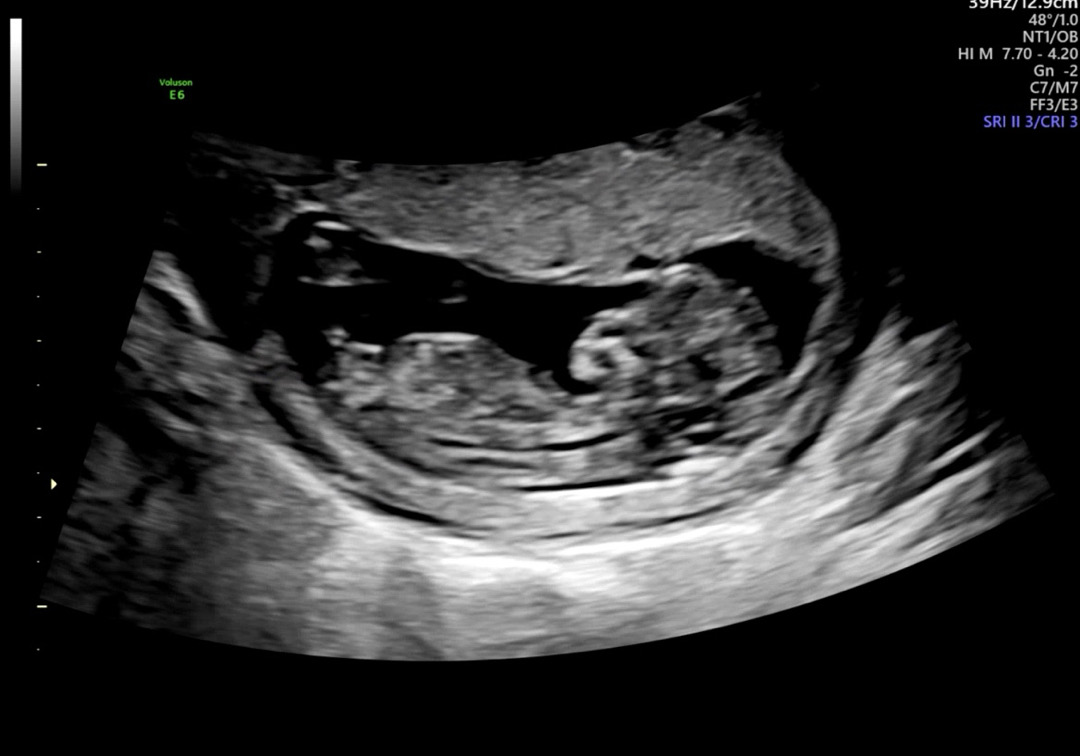

11주 각도법 성별이 너무궁금해요

11주 2주에 초음파 본건데 성별이 너무 궁금해요 첫째때랑 다른것 같으면서도 애매해서 의견나눠주세요:-)